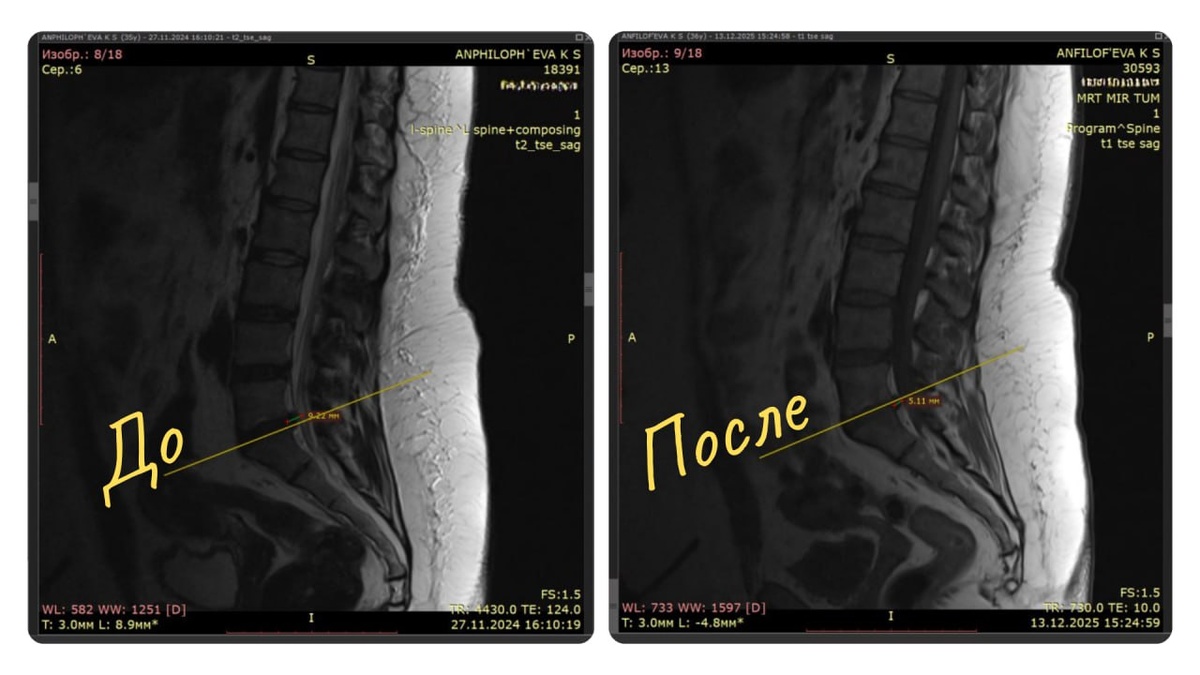

Делаю МРТ. Результат: 👨‍⚕️ грыжа 9,5 мм, которая полностью перекрывает левый корешок S1, плюс условия для сдавления соседних корешков и стеноз позвоночного канала.

Декабрь 2025, контрольное МРТ: грыжа уменьшилась до 5,5 мм. Она перестала давить на корешки. Стеноз ушёл.